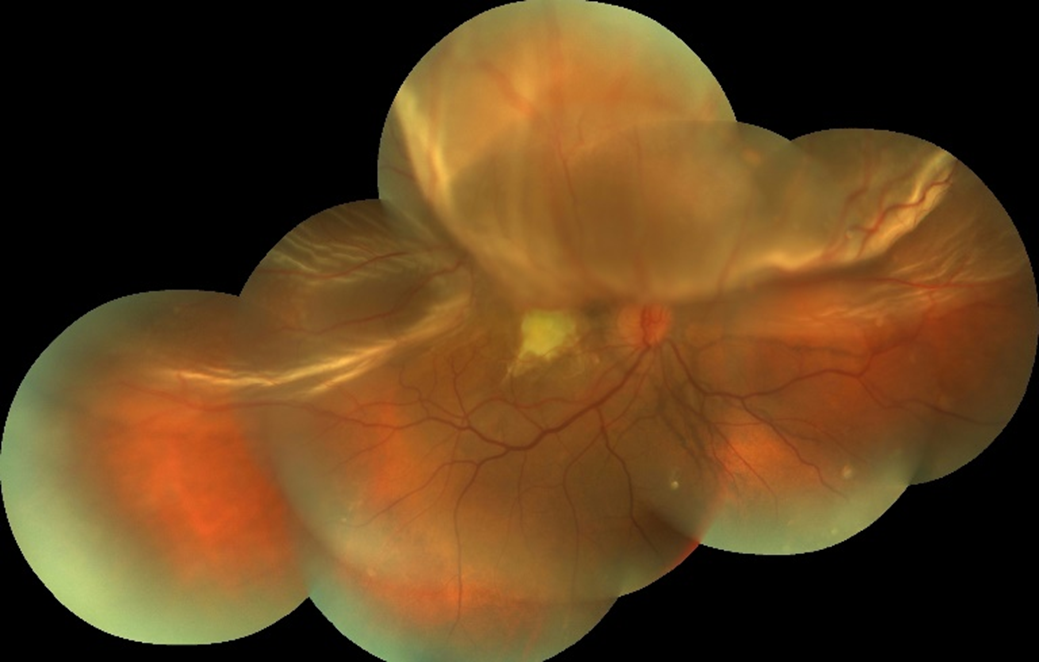

2026 Nisan Ayın Sorusu

Her iki gözde doğuştan bu yana görme problemleri olan 11 yaşındaki erkek hastanı ...